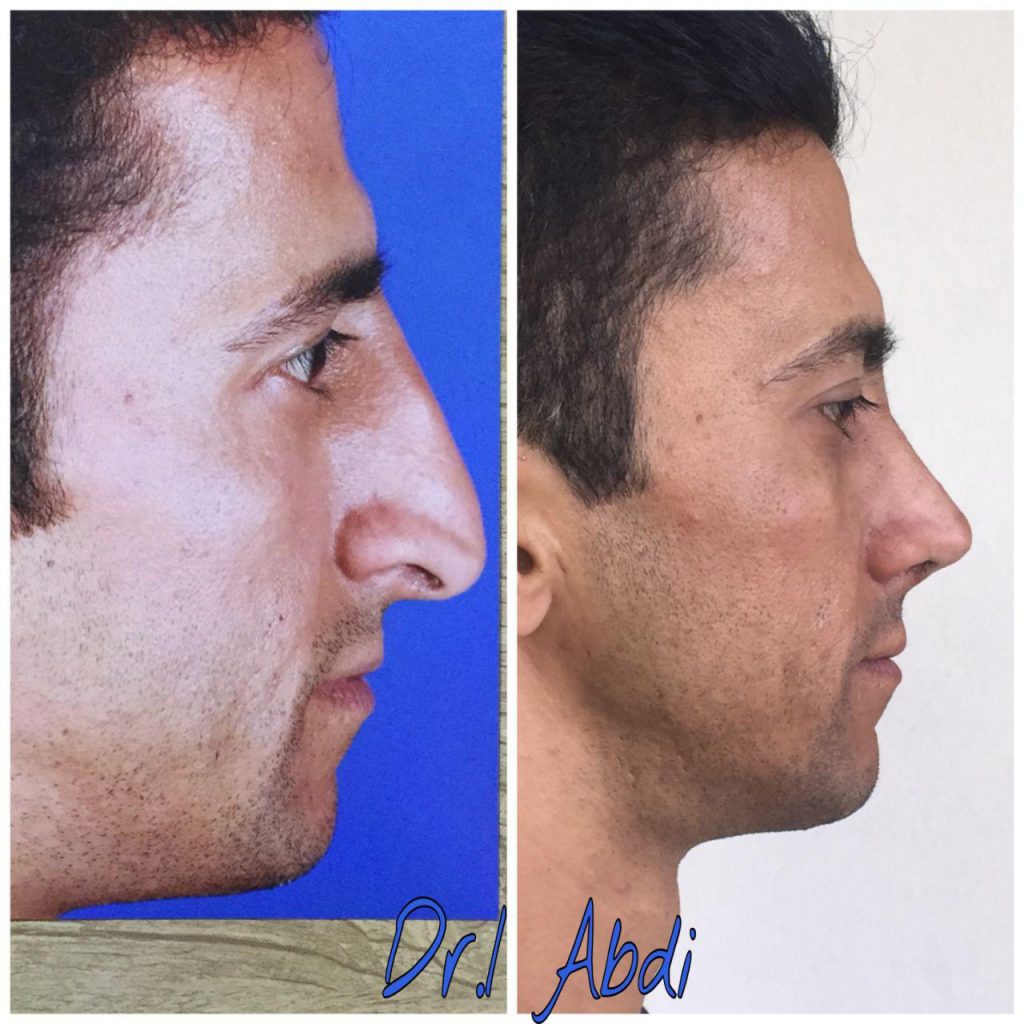

دکتر عیسی عبدی در رشت

دکتر عیسی عبدی در رشت

– متخصص جراحی فک , پلاستیک صورت و بینی

دکتر عیسی عبدی در رشت

جراحی فک , پلاستیک , صورت وبینی